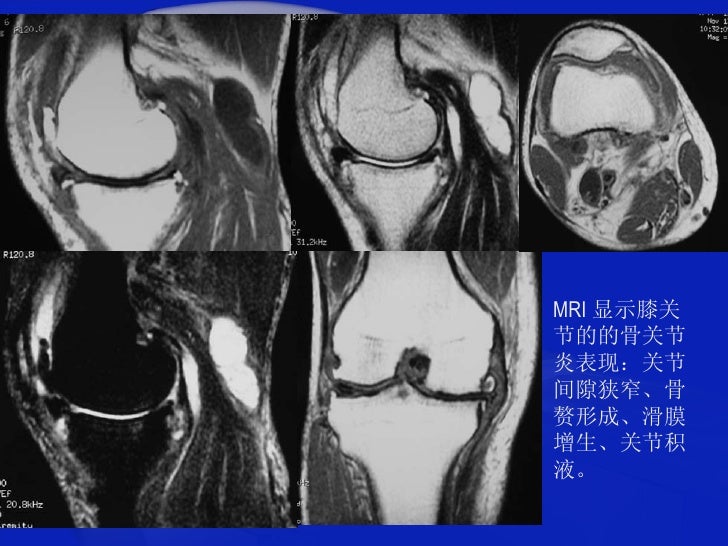

科学网 膝关节骨关节炎拍了x片还要做磁共振检查么 什么是膝骨关节炎磁共振mri检查的recht分级标准 高绪仁的博文

膝关节骨关节炎表现 治疗和常见误区有哪些 老中医张建福告诉你 每日头条

骨关节炎早期能治愈吗 知乎